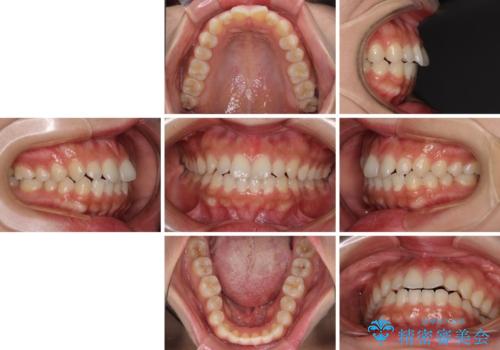

インビザラインを用いた上顎の部分矯正

- インビザライン・ライト

- 1年5ヶ月

- 上顎前歯の叢生を気にして来院された患者様です。

下顎前歯や上下奥歯の咬み合わせには殆ど問題がないため、上顎前歯のみを矯正する治療を提案しました。

ワイヤー装置でもインビザラインでも可能でしたが、前歯のみをきれいに排列するのであればインビザラインの方が仕上がりが良いので、インビザライン・ライトにて治療を行うこととしました。